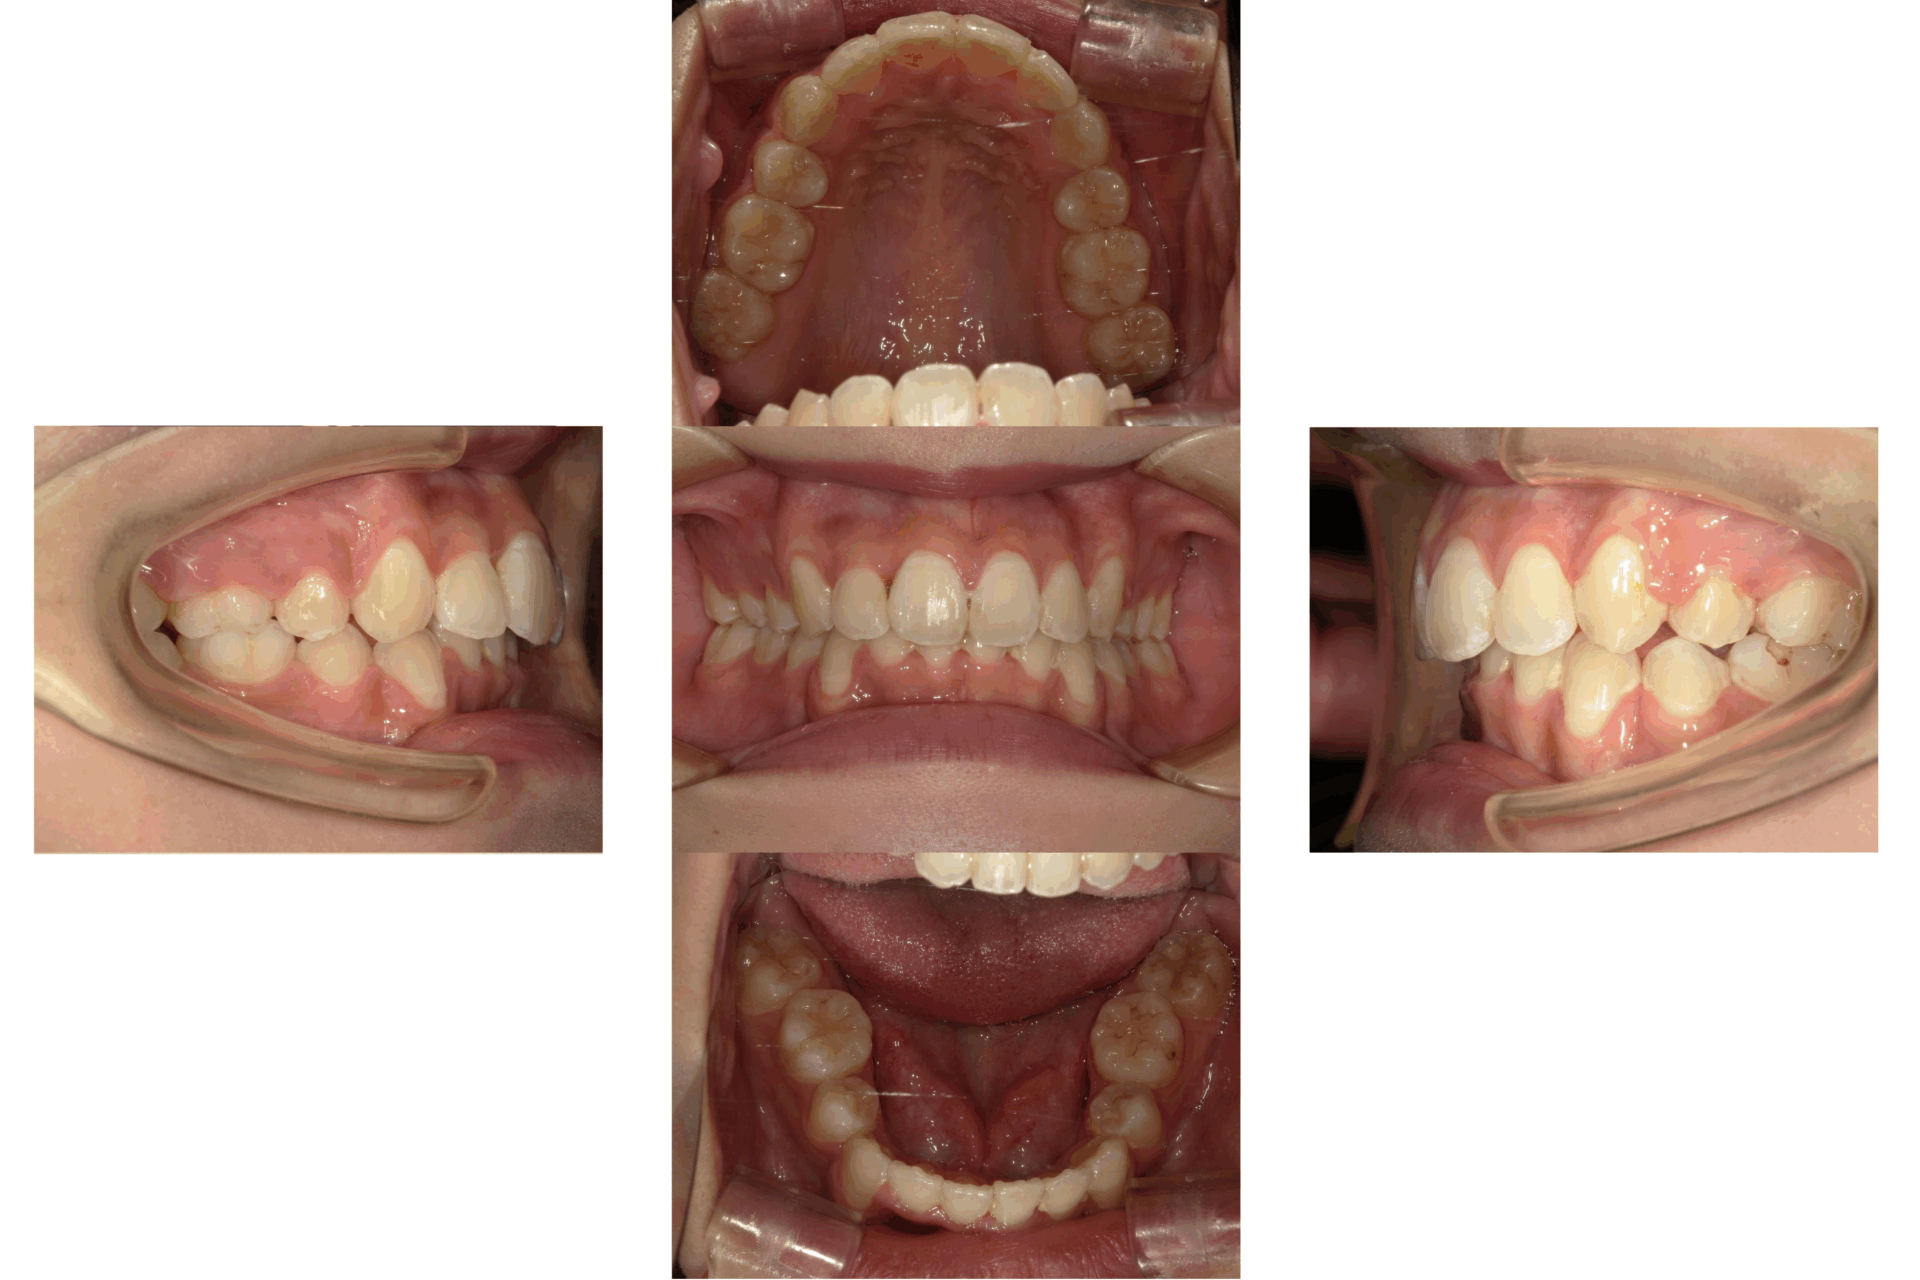

20代、男性、ワイヤー

| 施術内容 | 主訴:でこぼこで食べ物がよく挟まる。虫歯や歯肉炎に悩まされてきた。 詳細:ワイヤー矯正での歯並び改善 とても磨きやすくなったと満足されてます。 |

| 治療期間 | 16ヶ月(2/3現在 治療終了) |

| リスク・副作用 | ■リスク・副作用 ・治療の初期段階では、痛みや不快感が生じやすくなりますが、一週間前後で慣れます。 ・歯の動き方には個人差があるため、予想された治療期間より延長する場合があります。 |

| 費用 | ワイヤー矯正 60万円(税込660,000円) |